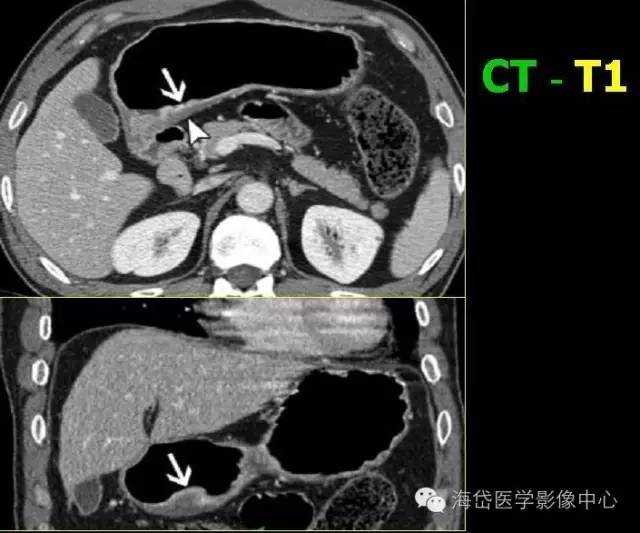

T1 腫瘤侵及黏膜固有層或黏膜下層 T1a 腫瘤侵及黏膜固有層;T1b 腫瘤侵及黏膜下層。

T1:低密度的粘膜層保持完整